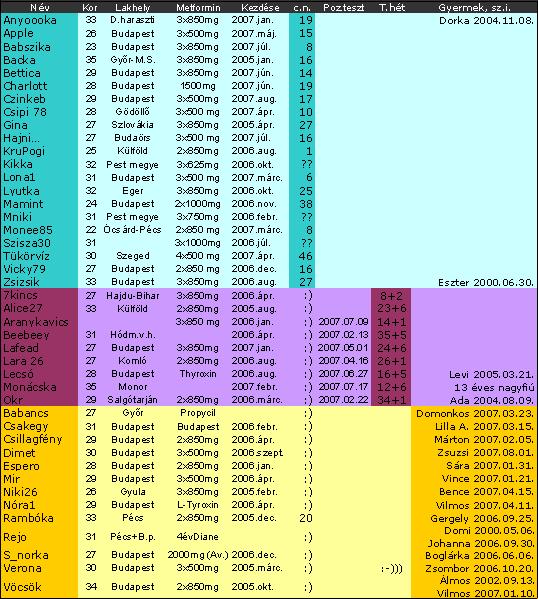

Ja és Verona GRATULÁLOK!! 23.hét!! jó, nagyon jó..remélem leszünk páran akiknek így sikerül a második baba! A kezdeti izgalmakat kihagytad